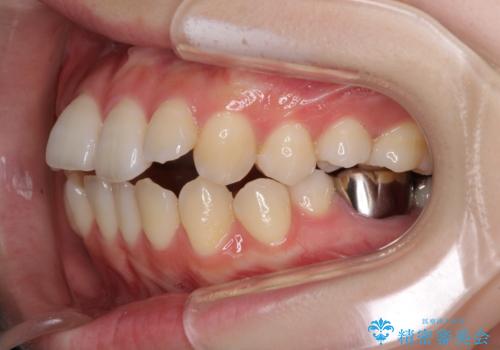

目立たない裏側矯正で突出感を改善 ハーフリンガル矯正

- 治療期間

- 4年6ヶ月

- 口元の突出感を気にして来院された患者様です。

上下左右の第一小臼歯4本を抜歯して口元を下げる治療計画としました。